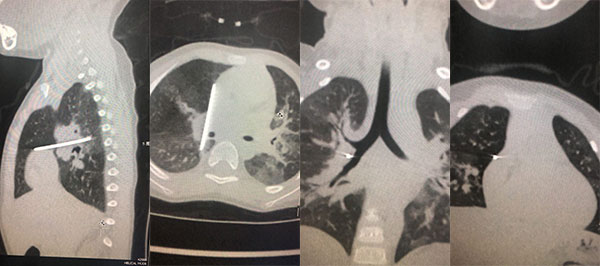

后续检查进一步显示,孩子胸腔内有一根疑似钢针的异物,孩子年龄小,异物长,针尖朝着心脏的方向,紧挨大血管和气管。心脏在跳动,肺部也随着呼吸在动,稍稍一个体位的变化或者深呼吸,都有可能造成针的移动,随时都有扎破血管的风险,后果不堪设想。

手术于当天下午13点30分开始,麻醉科滑蕾医生采用气管封堵器实施单肺通气,快速实现术侧肺组织萎陷。麻醉成功后,由介入肺科焦安夏主任团队进行气道探查,发现右上叶支气管局部粘膜凸起,考虑异物为外压所致。证实术前判断异物是从胸壁进入胸腔,决定行胸腔镜探查异物取出术。胸外科曾骐主任和陈诚豪副主任刷手上台、配合默契,在右侧胸壁快速建立3个直径5毫米手术切口,经过15分钟紧张的胸腔镜微创手术操作,快速并顺利自肺内将5厘米长的异物取出,手术顺利完成,没有出现大出血等并发症。